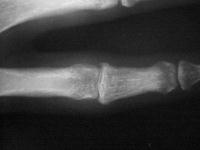

Range of motion not terrible, but...

Xrays show an apparently healed PIP fracture dislocation with dorsal subluxation - but concentric tracking of the abnormal palmar articulation.